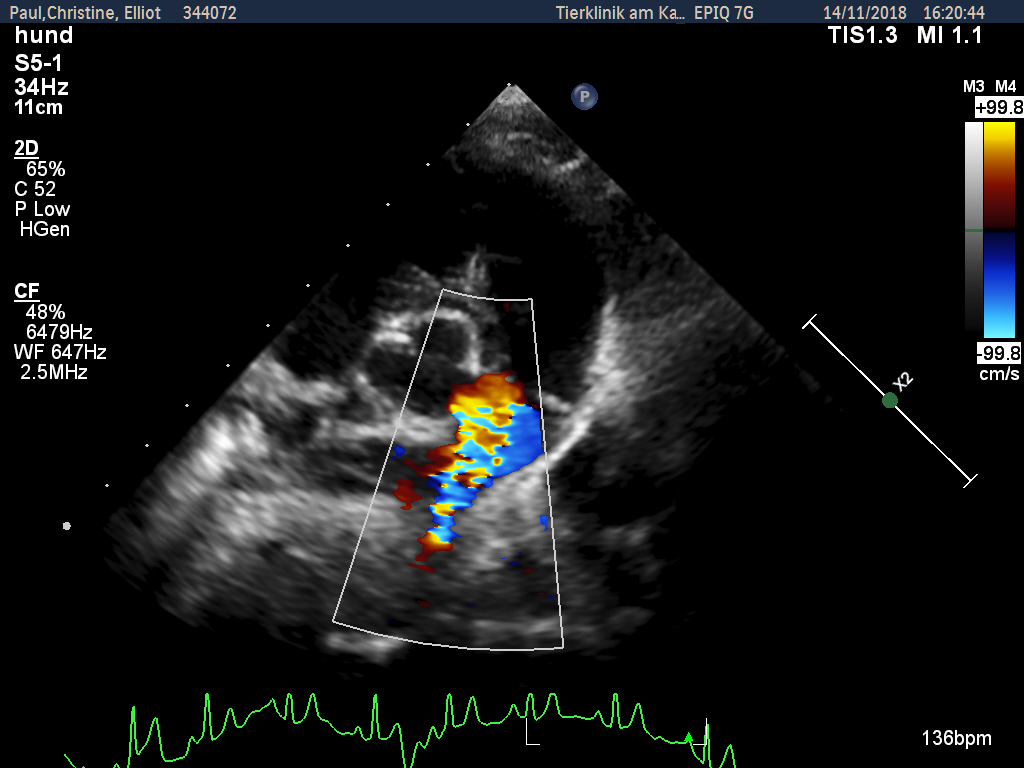

Zunächst wurde von den Kollegen - aufgrund des zeitlichen Zusammenhangs - eine Impfreaktion vermutet, woraufhin Elliot starke Schmerzmittel bekam. Allerdings besserte sich seine Lahmheit weder durch Schmerzmittel noch durch Kortison wesentlich. Da man äußerlich nichts feststellen konnte, wurde eine erste Röntgenuntersuchung des Rumpfes durchgeführt, bei der aber die Ursache leider nicht gefunden wurde. Als auch nach dieser weder Fieber noch Lahmheit verschwanden, wurde der Hund zur Spezialdiagnostik überwiesen. Es sollte nun bei uns in der Klinik erneut geröntgt und eventuell eine Computertomographie durchgeführt werden. Bei der Eingangsuntersuchung vor der notwendigen Narkose wurde ein kontinuierliches Herzgeräusch festgestellt. Dieses konnte nur unter dem linken Schulterblatt in Höhe des 2.-3. Zwischenrippenraumes auskultiert werden. An dieser Stelle war es aber sehr laut (Grad 5 von 6) und gut hörbar. Der untersuchende Kardiologe stellte einen klinisch relevanten PDA (Ductus arteriosus botalli persistens) fest, der sich schon in einem behandlungswürdigen Stadium befand. Daher war an eine Narkose zur Abklärung der Lahmheit an diesem Tage nicht zu denken.

Erfreulicherweise verschwindet die Erkrankung mit Ende des Knochenwachstums. Für Elliot zunächst aber das kleinere Problem. Ein PDA, wie er im Herzen von Elliot festgestellt wurde, verläuft für fast 2/3 der Welpen im ersten Lebensjahr tödlich. Daher muss dieser verschlossen werden. Bei dem PDA handelt es sich um ein Blutgefäß, welches sich nach der Geburt nicht ordnungsgemäß verschlossen hat. Deshalb fließt Blut auch nach der Geburt an der Lunge vorbei zurück in das linke Herz, welches sich daraufhin stark vergrößert.